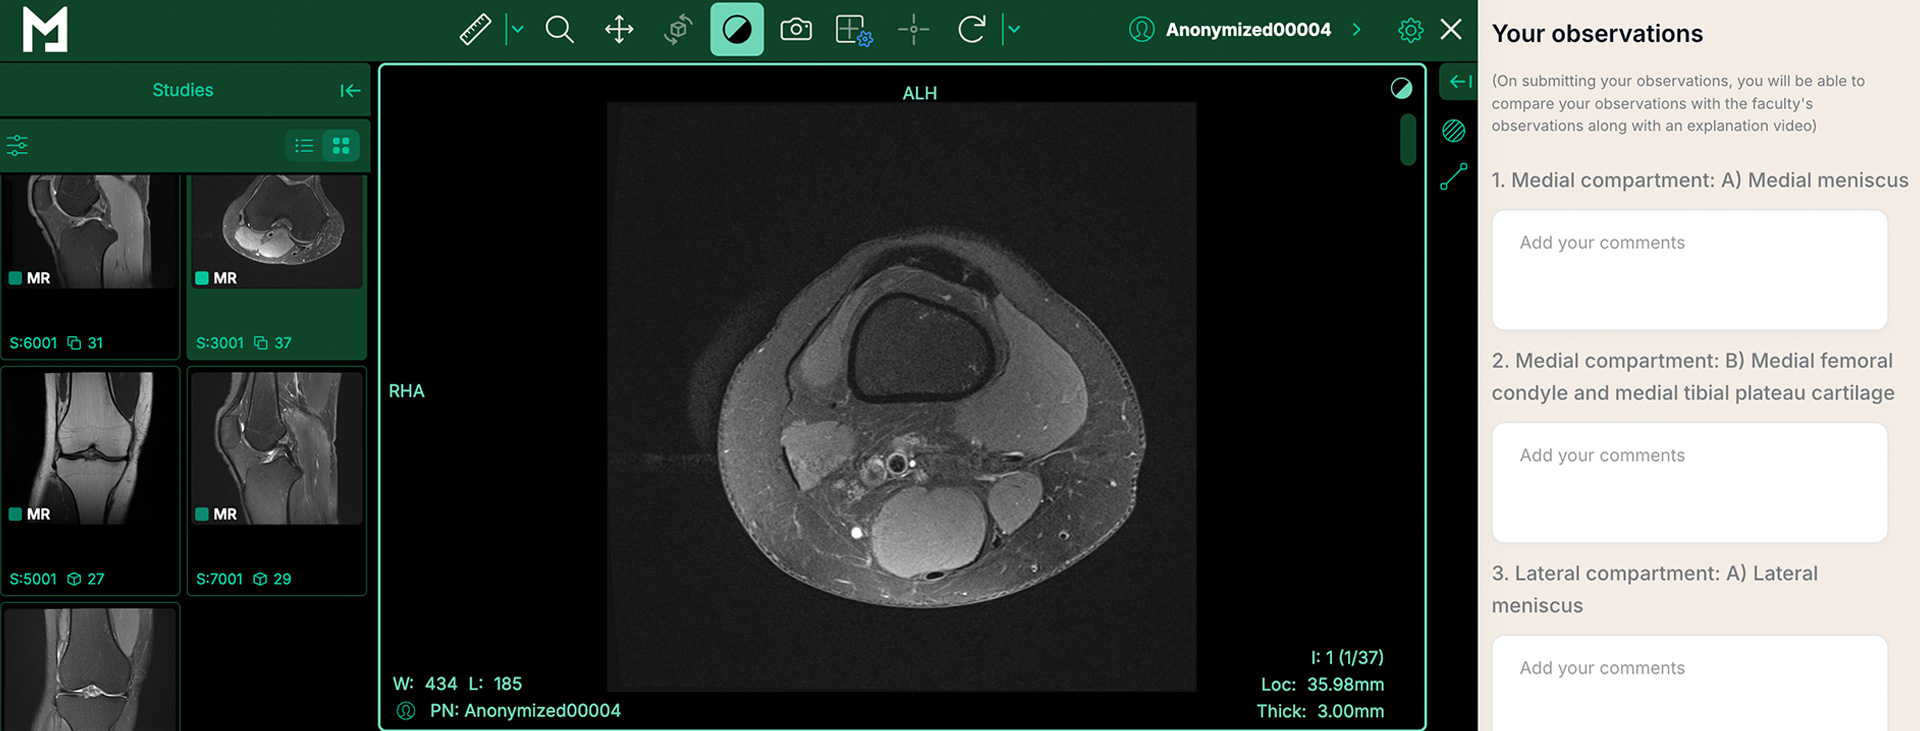

Fellows gain access to high-quality DICOM case studies, designed to simulate real-world clinical scenarios. These challenging cases are tailored to sharpen their clinical decision-making skills.

Leveraging cutting-edge imaging emulators, a user-friendly hub, and personalized program buddies to maximize learning outcomes.

EXPERT IMAGING EMULATOR